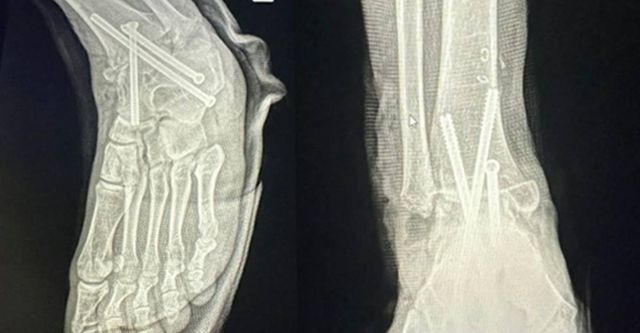

병원이 실수로 A씨의 멀쩡한 오른발 발목뼈를 절단해 철심 3개를 박은 모습 / 연합뉴스(A씨 제공)

A 씨는 지난해 3월 10일 서울의 한 병원에서 ‘발목 관절염 삼중 유합술’을 받았다. 2시간여의 수술이 끝나고 마취에서 깨어났다. 그런데 뭔가 이상했다. 마취에서 깨어나 보니 왼발은 가볍고 오른발이 이상할 정도로 무거웠다. 알고 보니 병원이 실수로 멀쩡한 오른발을 수술하면서 철심 3개를 박아 넣었던 것.

정형외과 전문의 출신 이용환 변호사는 ‘실화탐사대’ 인터뷰에서 다른 의견을 내놨다. 그는 “뼈와 뼈 사이 간격이 좁아져야 관절염이 생기는 건데 (오른발의) 다른 뼈들은 다 정상이다”라고 밝혔다.